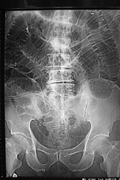

Differentiating large and small bowel

| Location | Size | Lines |

| Small bowel | 3 cm | All the way through the bowel (plica circulares) |

| Colon | 6 cm | Only halfway through the bowel (haustra) |

| Cecum | 9 cm |